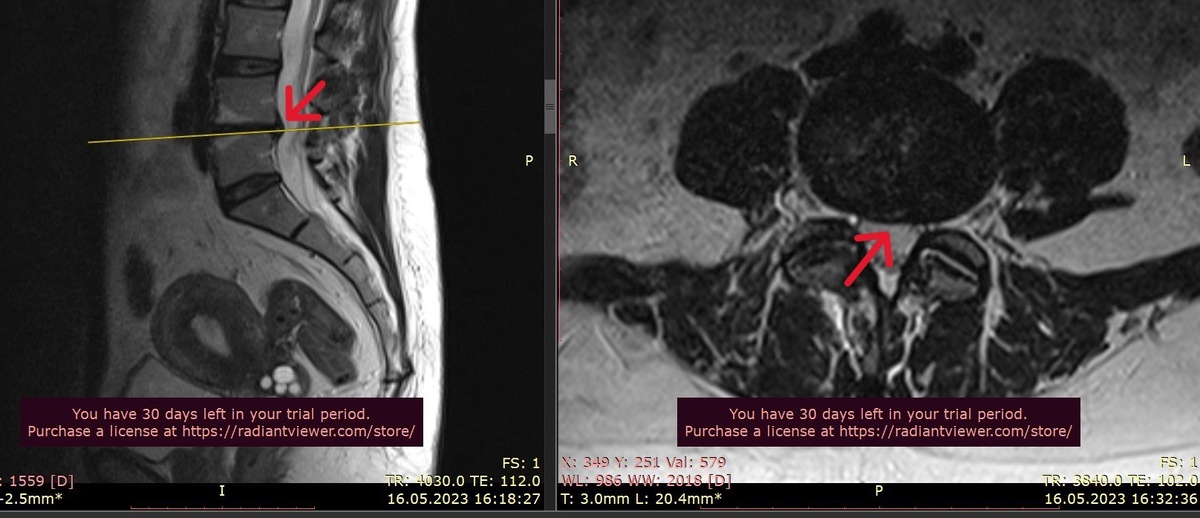

На МРТ обнаружили достаточно большую медианную грыжу на уровне L4–L5.

А на контрольном МРТ грыжа уменьшилась.